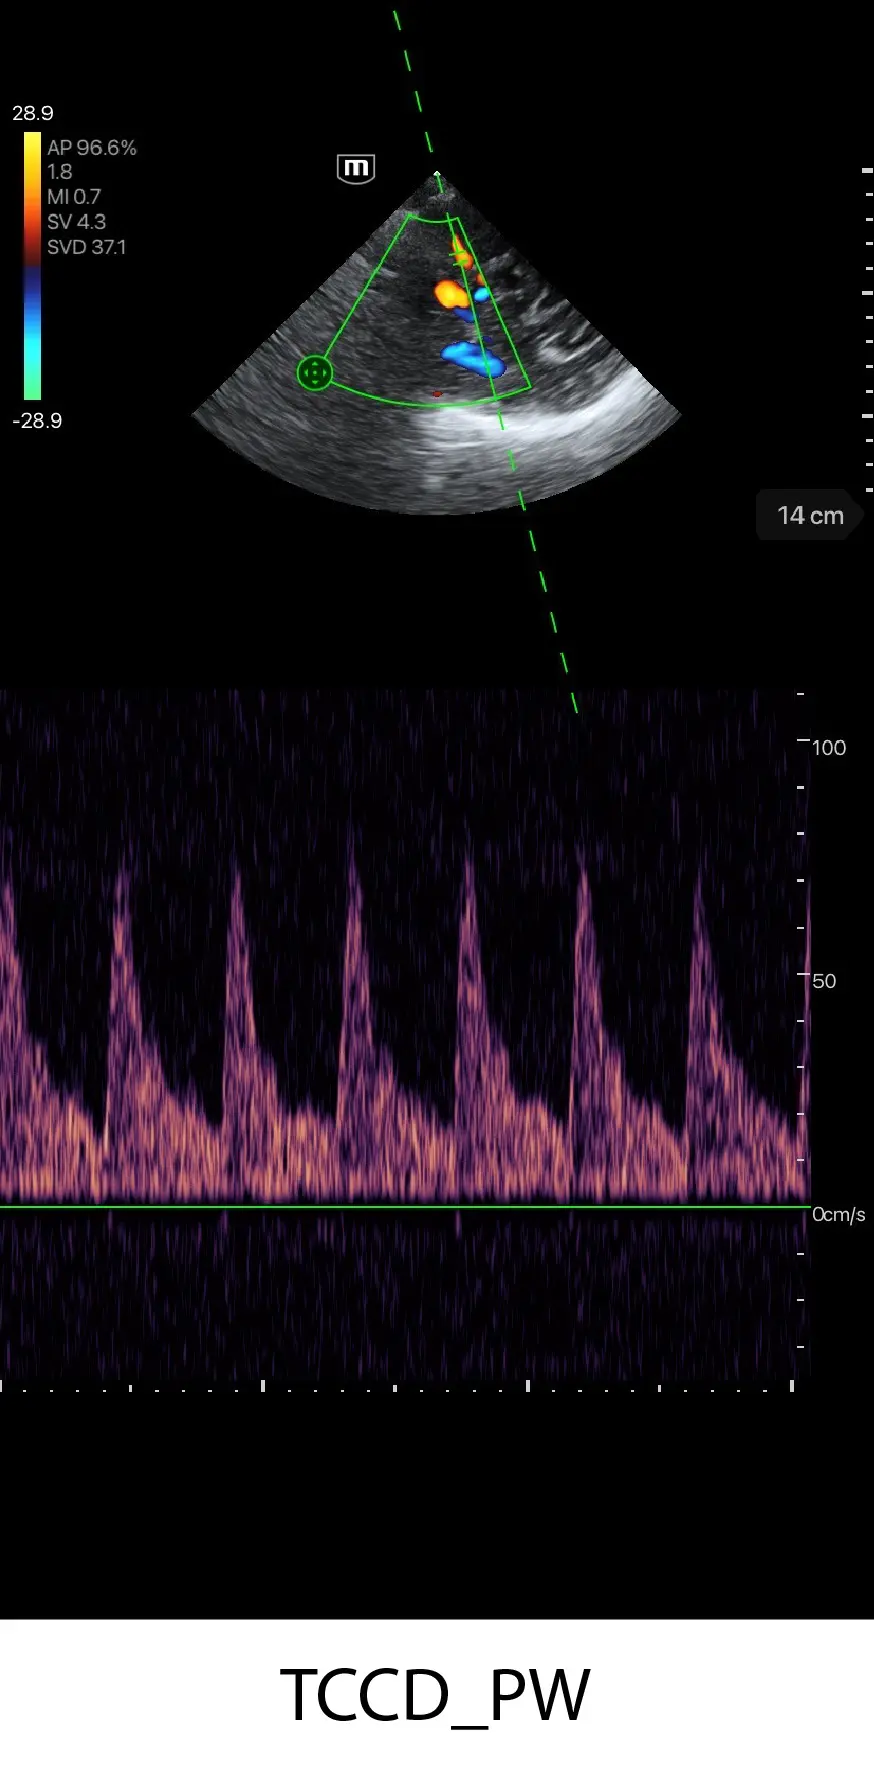

PW mode

PW Auto Trace

Пулсов доплер с автоматично очертаване на вълната - за измерване на скоростта на кръвния поток.

FAST/eFAST, фокусирани сърдечни, коремни, транскраниални и основни белодробни

Работа в отделението, консултация: сърдечна, белодробна, FAST/eFAST, оценка на обема, TCI

Бърза диагностика на сърдечната функция; скрининг за сърдечна патология

Клинични снимки